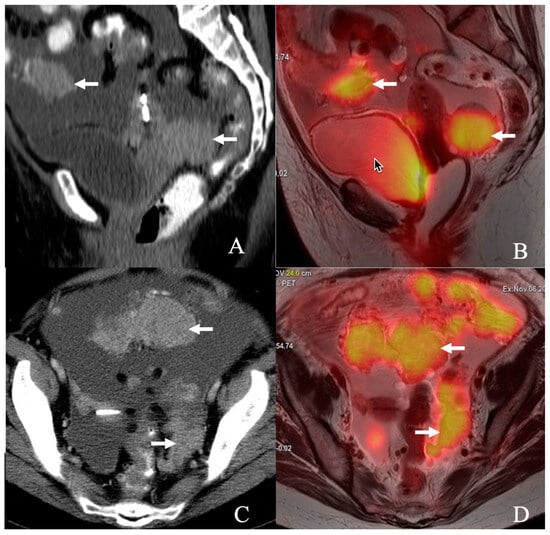

Traditionally, contrast-enhanced computed tomography (CECT) has been the imaging cornerstone in evaluating ovarian cancer due to its widespread availability and established role in oncologic imaging [3]. It has been used to predict suboptimal resection, with a sensitivity ranging from 28% to 87% and a specificity ranging from 43% to 100% [4]. One recent study showed high predictability of suboptimal debulking using CT [5]. However, emerging hybrid imaging techniques like positron emission tomography/magnetic resonance imaging (PET/MR) have shown promise in oncologic imaging, combining the functional capabilities of PET with the superior soft-tissue contrast of MR [6]. This dual capability positions PET/MR as a potentially superior modality for detecting peritoneal and small-volume disease, critical for accurate staging and treatment planning in ovarian cancer (Figure 1).

Figure 1. A 68-year-old female presents with adenocarcinoma, Mullerian primary/high-grade serous-type ovarian carcinoma with peritoneal carcinomatosis. (A) Sagittal, (C) axial contrast-enhanced CT, and (B) sagittal, (D) axial T2-weighted PET/MR images show FDG-avid peritoneal masses (arrow) in the pelvis and diffuse ascites.